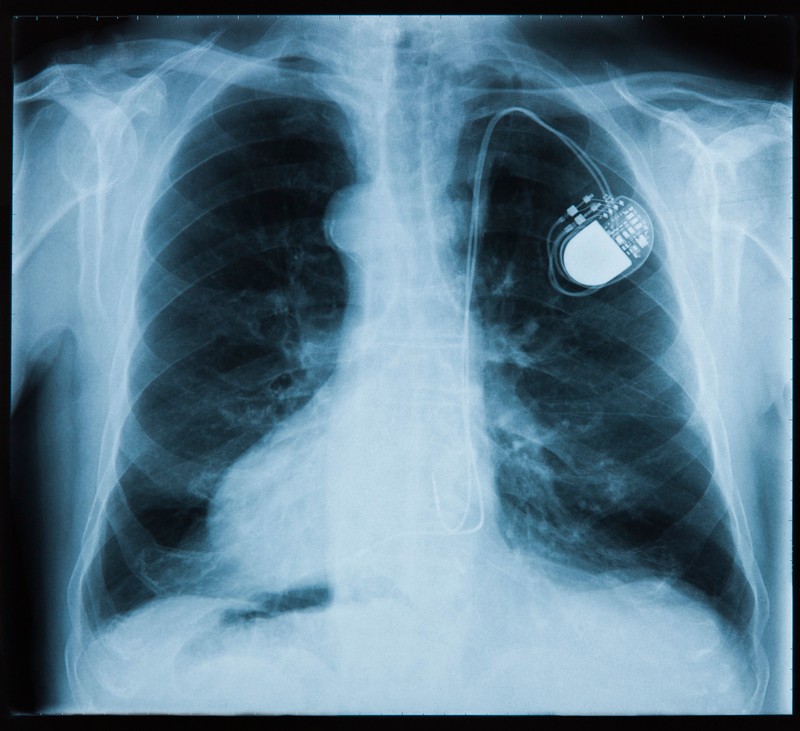

Szív- és érrendszeri betegségek